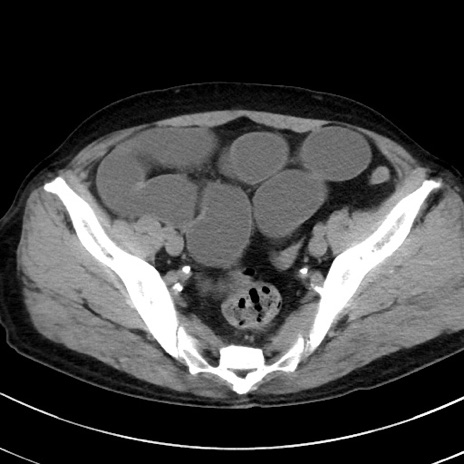

冠状断像

【症例】70歳代 男性

【主訴】腹痛・嘔吐

【現病歴】昨晩より、嘔吐・腹痛あり。今朝になっても嘔吐あり。来院。

【既往歴】心臓バイパス手術、開腹胆摘、腸閉塞

【身体所見】BP 107/71mmHg、HR 116/min、腹部:平坦、軟、下腹部に軽度圧痛あり。反跳痛なし。

【データ】WBC 15100、CRP 0.32